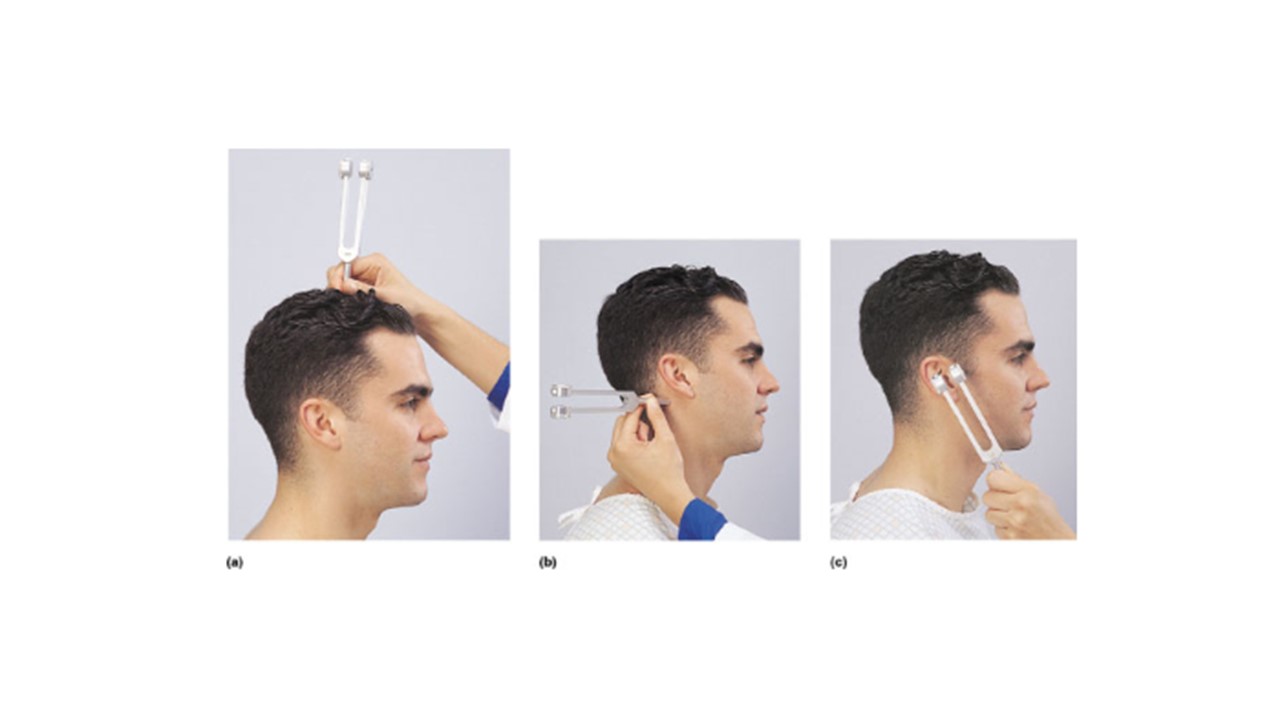

Which lettered image(s) above demonstrates the proper administration of the Weber Test?

a

If the man in image a hears the tone in his left ear but not his right he is experiencing __________________ deafness in his right ear.

sensorineural